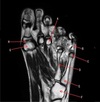

6

A

1

3

Perfectly

What is letter A?

How well did you know this?

2

5

Q

HEAD OF HUMERUS

Not at all

4

9

What is letter D?

ANTERIOR LABRUM

12

What is letter C?

POSTERIOR LABRUM

What is letter B?

What is letter E?

What is letter F?

What is letter K?

What is letter G?

What is letter H?

What is letter J?

What is letter D